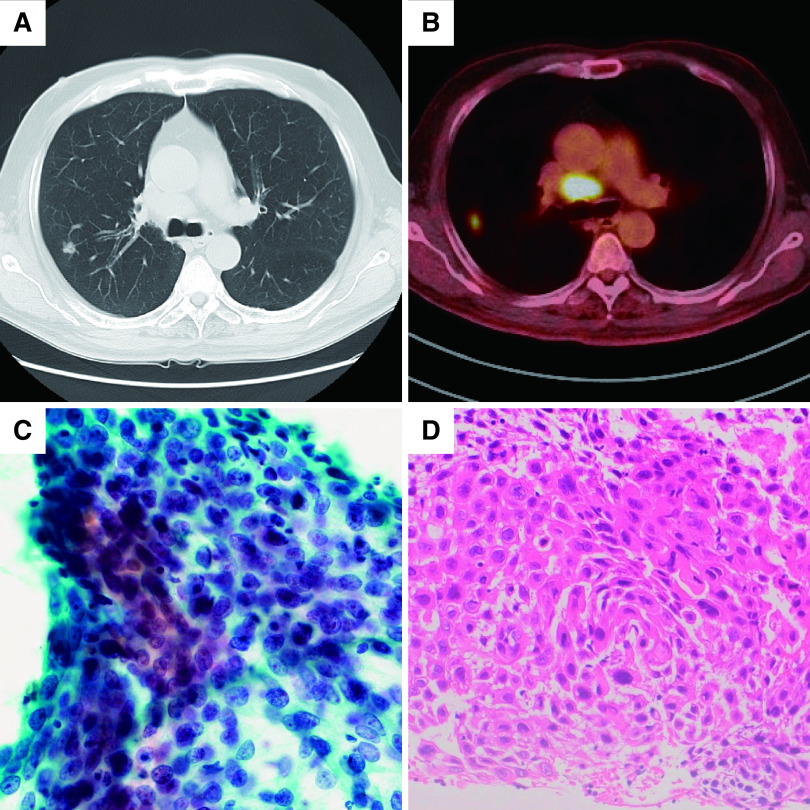

A 71-year-old man was diagnosed as having right primary lung squamous cell carcinoma, clinical stage IIIA, but he refused treatment. However, the right upper lobe nodule and lymph node (LN) #4R showed gradual shrinking without treatment. Four years after the diagnosis, a new nodule was detected in the left lung field. We considered that this new nodule might be metachronous primary lung cancer, and hence resected it for diagnosis and treatment. The tumor in the left lung was diagnosed as basaloid squamous cell carcinoma, and that in LN #4R was diagnosed as squamous cell carcinoma with keratinization. Therefore, the patient was diagnosed as having metachronous primary lung cancer that developed during the spontaneous regression of locally advanced lung cancer.